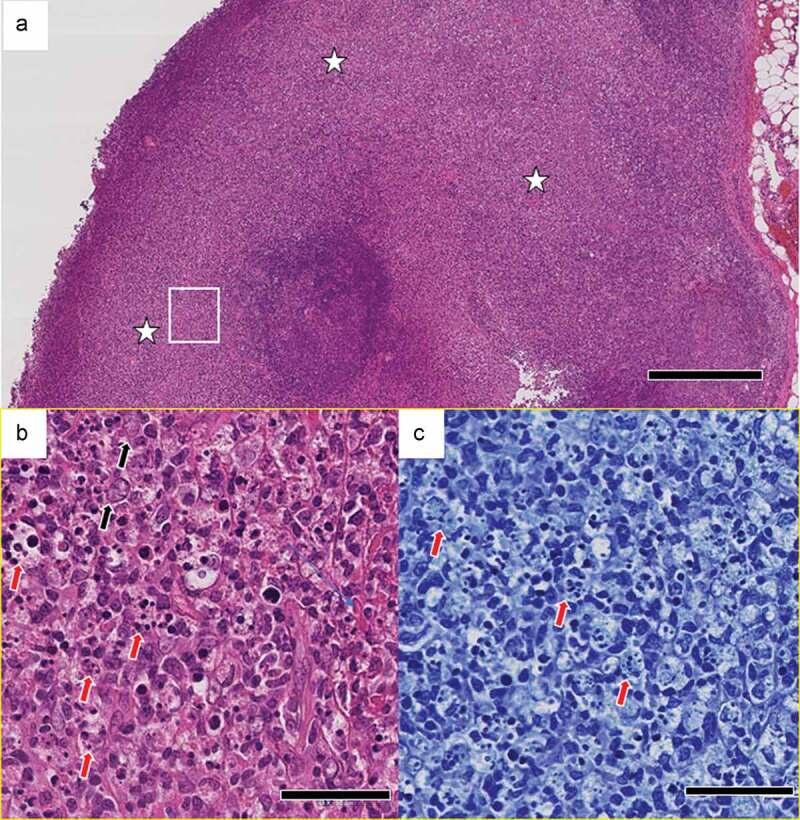

Following COVID-19 vaccination, ipsilateral axillary and cervical lymphadenopathy may occur, called vaccine-related hypermetabolic lymphadenopathy, which is considered reactive lymphadenopathy. We report here a case of Kikuchi-Fujimoto disease, which occurred three months after vaccination with COVID-19 vaccine. The patient had cervical and axillary lymph node enlargement and a short-term fever that resolved spontaneously after the first and second vaccines. On the 90th day after the first vaccination, the patient developed a high fever and pathologically diagnosed necrotizing lymphadenitis in the axilla, which was diagnosed as Kikuchi-Fujimoto disease. Gallium scintigraphy showed localized swelling and strong uptake in the ipsilateral axilla. It implies the possibility of Kikuchi-Fujimoto Disease in axillary drainage lymph nodes in association with COVID-19 vaccine. Although only a few cases have been reported so far, this case is novel because of its later onset and diagnosis based on pathological and gallium scintigraphy imaging findings.

接种 COVID-19 疫苗后,可能会发生同侧腋窝和颈部淋巴结病,称为疫苗相关高代谢性淋巴结病,被认为是反应性淋巴结病。我们在此报告一例 COVID-19 疫苗接种后三个月发生的 Kikuchi-Fujimoto 病。患者出现颈、腋窝淋巴结肿大和短期发热,在接种第一和第二剂疫苗后自发消退。在第一次接种后第 90 天,患者出现高热,腋窝病理诊断为坏死性淋巴结炎,诊断为 Kikuchi-Fujimoto 病。镓闪烁显像显示同侧腋窝局部肿胀和摄取增强。这提示 COVID-19 疫苗接种后与腋窝引流淋巴结相关的 Kikuchi-Fujimoto 病的可能性。尽管到目前为止只有少数病例报道,但由于其发病较晚,且基于病理和镓闪烁显像影像学发现进行诊断,因此该病例具有新颖性。